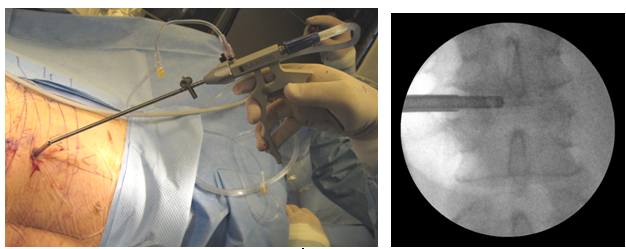

Figure 14 Discectome for irrigation and suction of debris after laser application and fluoroscopic view.